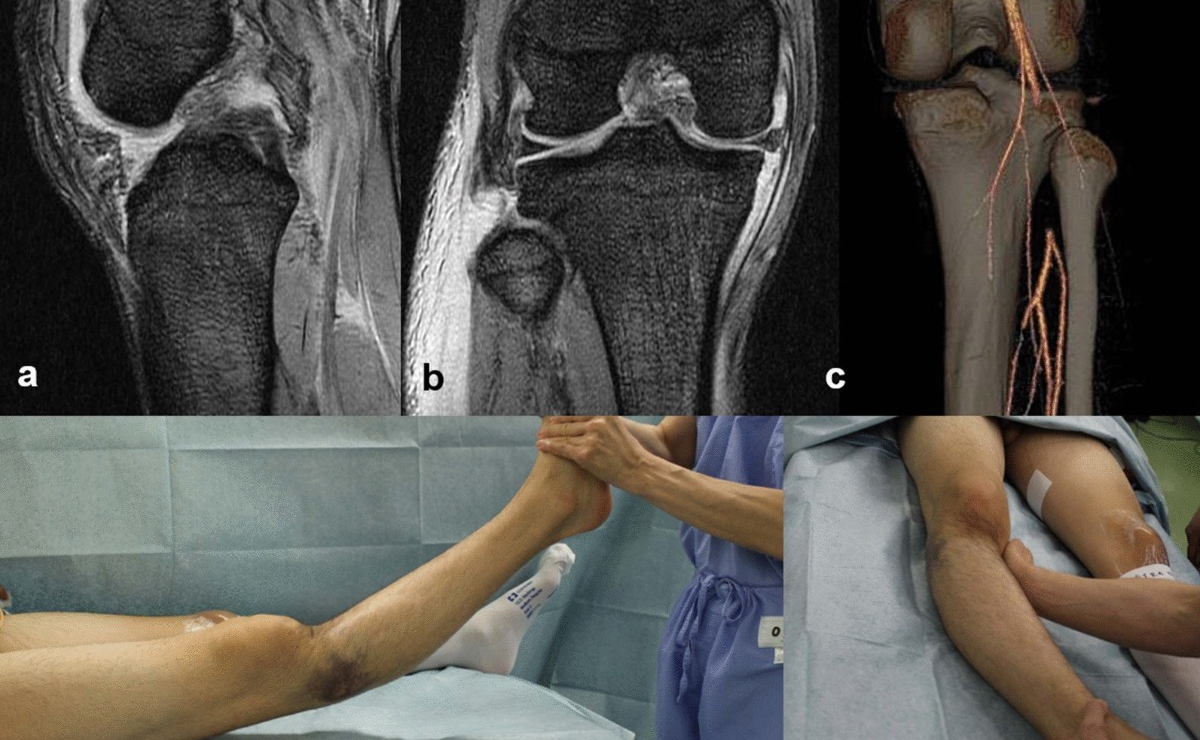

A complex multiligament injury occurs when two or more of the major knee ligaments (ACL, PCL, MCL, or LCL) are torn simultaneously. These injuries are often the result of high-energy trauma, such as sports collisions or vehicular accidents, and require a highly specialized approach to restore knee stability and function. Dr. Sahil Lombar is an expert in managing these severe knee injuries, utilizing advanced diagnostic tools and surgical techniques to provide comprehensive care.

Surgical reconstruction for multiligament injuries often involves staged or combined procedures to repair or replace the damaged ligaments using grafts. Dr. Lombar’s approach focuses on restoring the natural biomechanics of the knee joint while ensuring a structured rehabilitation plan. His goal is to help patients regain full mobility and return to their daily activities or sports through precise surgical intervention and personalized post-operative recovery protocols.